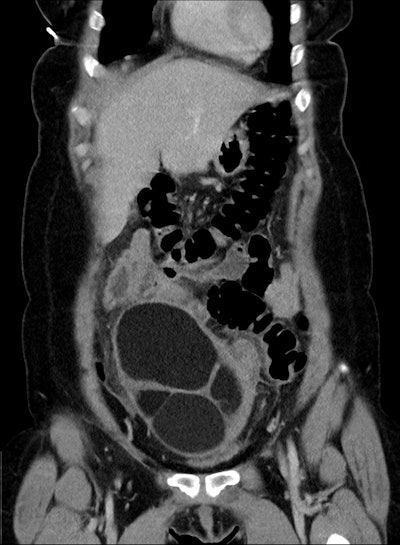

CT coronal; 25-year-old woman -- a large cystic mass in the anterior mid pelvis with smooth hyperdense borders. It converges to the right at a focal area of vascular twisting (whirlpool sign).All figures courtesy of the Medical Imaging Department, Mackay Base Hospital, Mackay, QLD, Australia, and the RANZCR 2025 annual scientific meeting.

Large ovarian cystic masses were present in both cases; the authors underscored that these are a known risk factor for ovarian torsion, and thus an important finding for diagnosis.

In the first case presented, CT showed a large right-sided adnexal cystic mass with evidence of a twisted vascular pedicle referred to as the “whirlpool sign,” suggestive of ovarian torsion. CT in the second case also showed a large lesion, which appeared to originate from a left-sided pedicle.